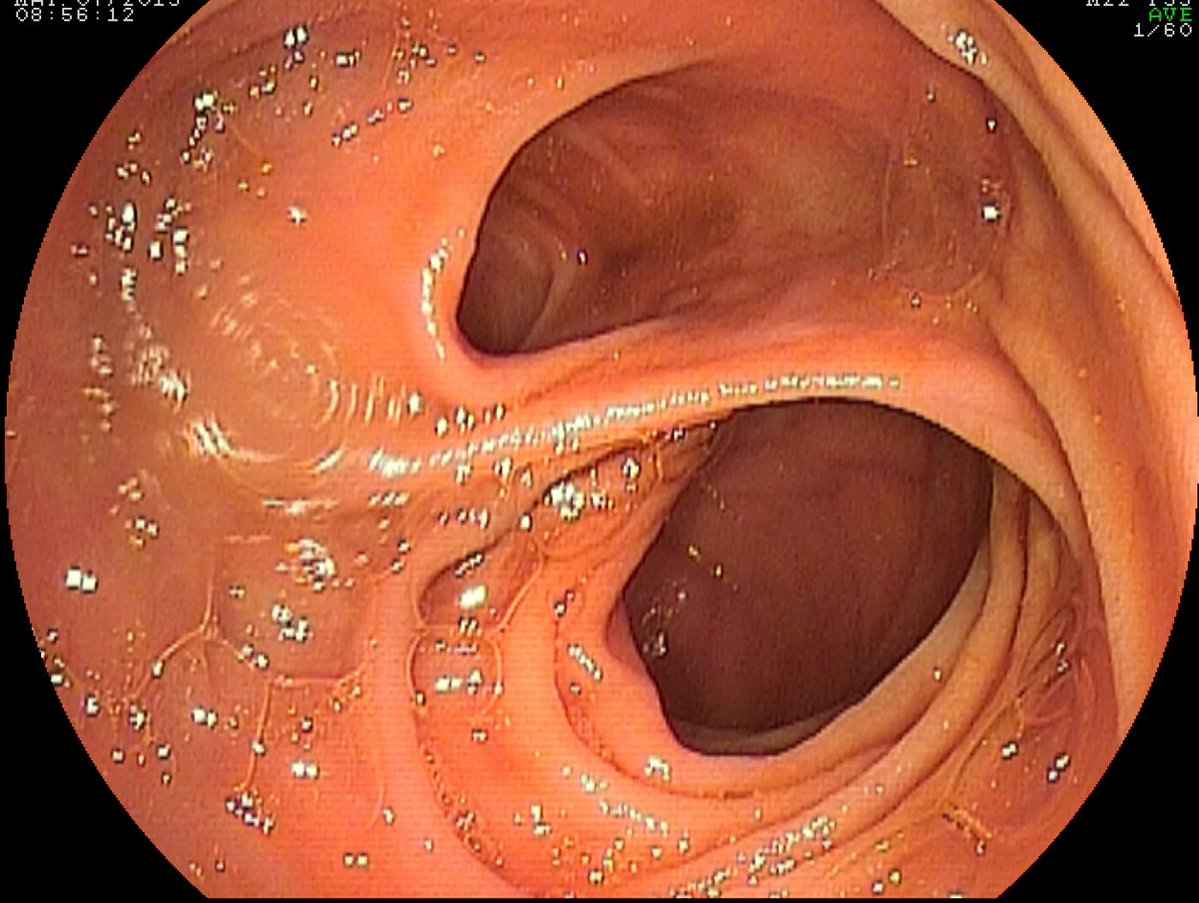

@EndoCollabcom

EndoCollab™ | GI Endoscopy Community

20 hours

This 55-year old patient underwent retrograde double balloon enteorscopy for recurrent "lower" gastrointestinal bleeding (hematochezia) and was found to have this in the ileum, about 80 cm proximal from the ileocecal valve. What is your diagnosis? Reply below for the answer

12

11

64